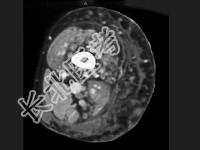

- 单项选择题男,16岁, 大腿可触及柔软、无痛性肿块,结合图像, 最可能的诊断是 ( )

A、滑膜肉瘤

B、脂肪肉瘤

C、脂肪瘤

D、血管瘤

E、淋巴管瘤